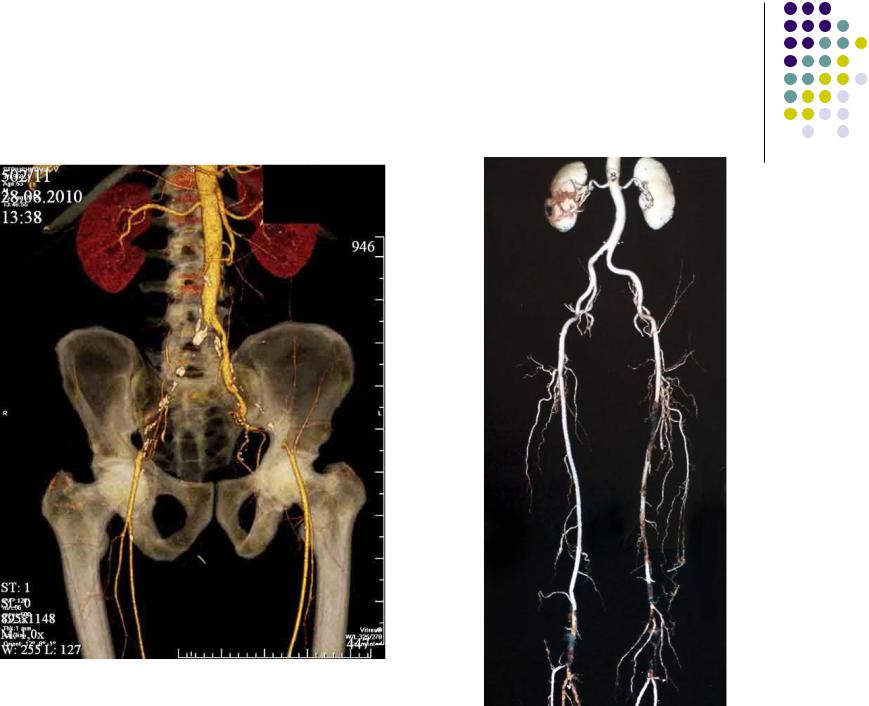

МСКТ ангиография при облитерирующем атеросклерозе